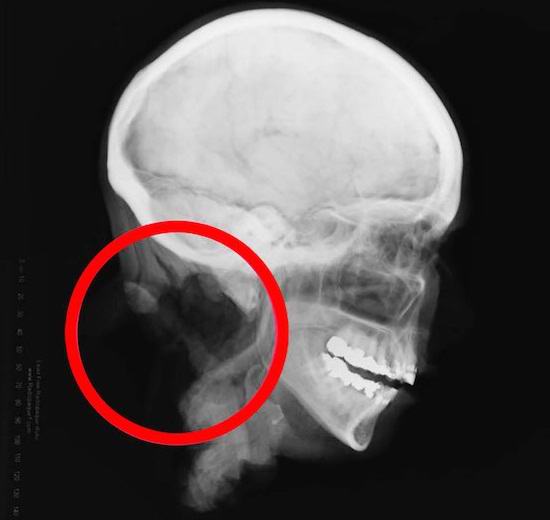

Az a szakasz, amely elválasztotta a fejet a testétől (ami még mindig nem volt lehetséges) találni) ügyes: rendkívül sima és pontos. Hátralévő csigolyák szépen eltávolítva a nyaki gerincről. Ez arra késztette a nyomozókat az ötlet, hogy egy bűnöző profi sebészeti készségek. Nem lehetett azonosítani a nőt: be sem a fogainak öntése, sem a DNS-elemzés, sem a Jane médiaportrék Dow.

Tovább – még érdekesebb és rosszabb. A kriminalisztikai szakemberek akartak megvizsgálja az elhunyt szemét, de meglepődve látta, hogy a szem a koponyában nem volt alma. Ehelyett a pirosokat helyezték a pályára. gumilabdák vékony lencsékkel. Először felmerültek a szakemberek verzió, amely szerint a szemét donor célokra távolították el, ám ez okozta kételkedik. Miért cserélje ki a szemét ilyen “kozmetikumokkal” protézisek “? Úgy tűnt, hogy a titokzatos bűnöző meg akarta tartani ezt a fejet kiállításként vagy dekorációként. A helyi orvosok még soha nem láttak ilyet.

A szakértők megvizsgálták ezeket a balzsamozott fejeket, és odamentek arra a következtetésre jutnak, hogy úgy néznek ki, mint Jane Doe feje. Különösen így vannak a nyaki csigolyákat mesterségesen eltávolítottuk, és a behelyezett csípőket megtaláltuk a szemek. Ez utóbbi azonban a következőképpen magyarázható: szem ne tegyék balzsamot jól, úgy, hogy a fej néz ki mint az élethez, szükségünk van műszem szemgolyóra is. Sajnos ezekre a két feje nem végezte el azonos alapos vizsgálatot, mindazonáltal minden azt jelezte, hogy az új leletek megegyeznek a fejjel Jane Doe